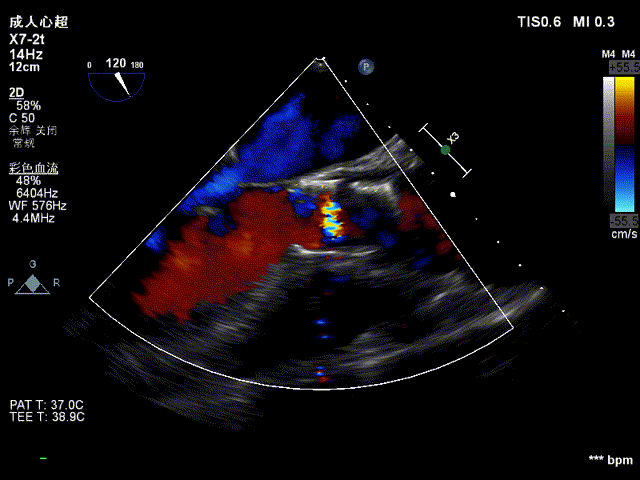

超声看位置合适,无反流